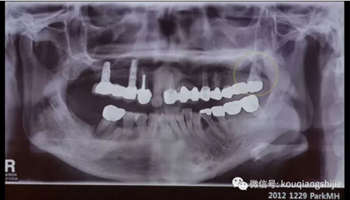

這個(gè)患者在2012年的時(shí)候#17已經(jīng)是需要拔除的情況,但是因?yàn)榛颊咭蟊A?,所以我們進(jìn)行保守治療

4年后患者再次就診,要求拔出

這時(shí)候我們可以看到患牙周?chē)呀?jīng)沒(méi)有任何骨壁。

我們看一下#27部位的拔牙創(chuàng)

你會(huì)覺(jué)得覆蓋在拔牙創(chuàng)上部分的是肉芽組織嗎?

我個(gè)人覺(jué)得不是,我覺(jué)得他就是上面我們定義的拔牙窩線性黏膜組織